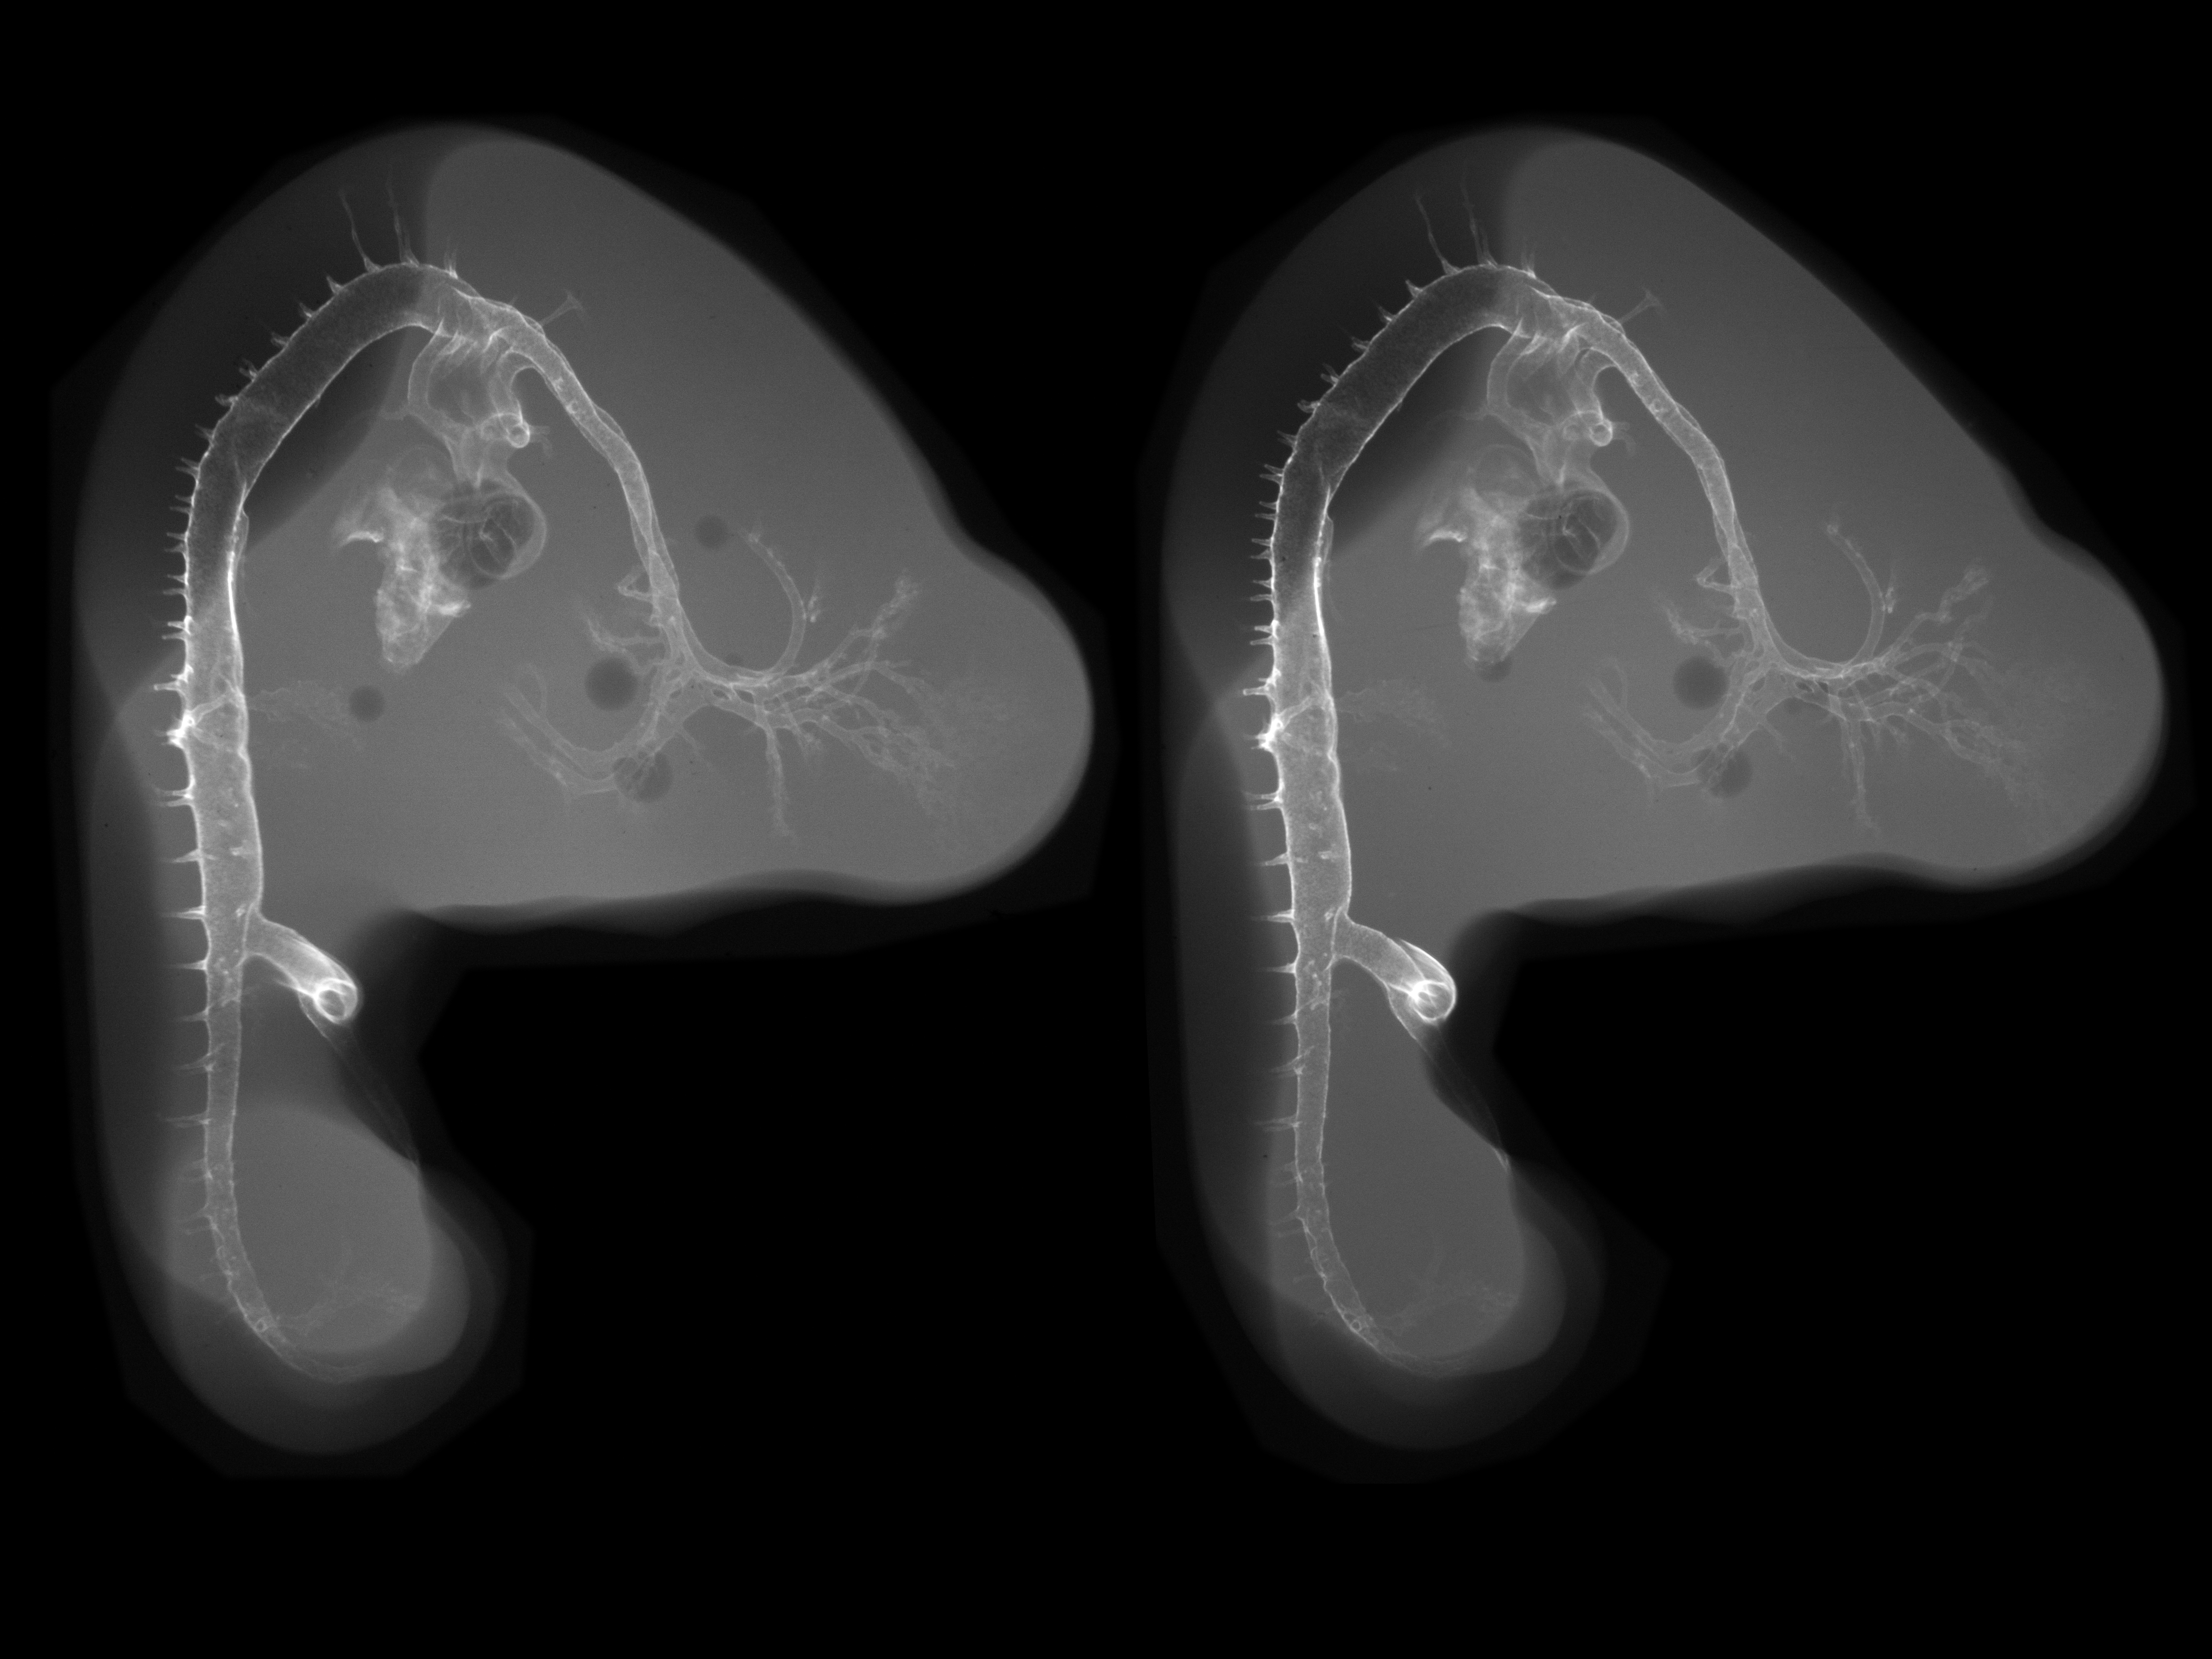

Chick Embryo Microangiography

Hamburger-Hamilton (HH) Stage 23 (approx. 4 days)

Stereo X-Ray Micrographs